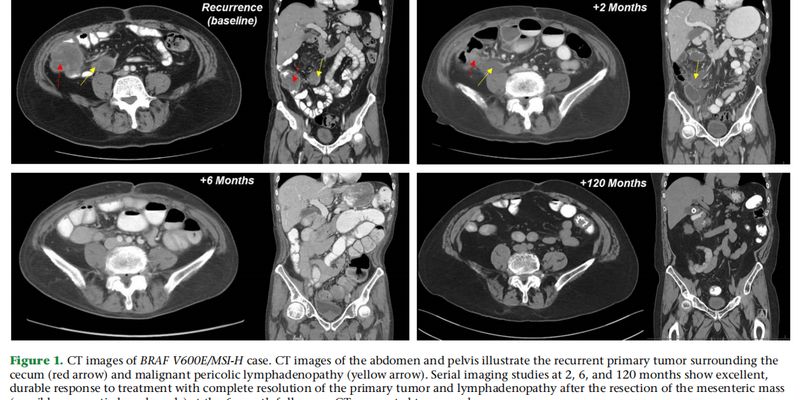

一名BRAF V600E突变且MSI-H的转移性结直肠癌患者,在接受维莫非尼、西妥昔单抗联合化疗后,竟实现了长达十年的完全缓解!这一罕见病例揭示了靶向联合治疗的巨大潜力。了解该方案的疗效、副作用及相关药物的购买渠道,为治疗带来新希望。 Read More... "十年完全缓解!靶向药维莫非尼如何攻克BRAF V600E突变结直肠癌?"